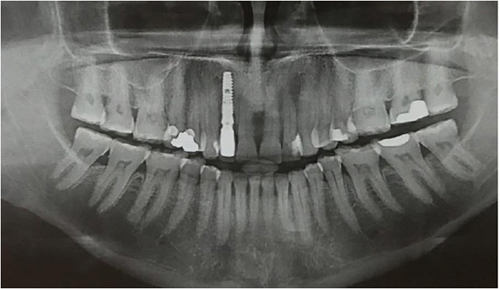

Після того, як виключені всі протипоказання, проводяться стандартні для всіх хірургічних втручань лабораторні дослідження – загальноклінічний і біохімічний аналіз крові, визначаються показники згортання крові, а також аналізи на ВІЛ-інфекцію, гепатит В і С, сифіліс. З інструментальних методів дослідження використовується рентгенографія (ортопантомограмма – панорамний знімок зубів), при необхідності – КТ або МРТ верхньої і нижньої щелепи.

КТ діагностика ротової порожнини

Комп’ютерна томографія зубів – досконалий метод дослідження, який дозволяє лікарю визначати параметри будови зубощелепної системи, що дає більше інформації про аномальні патології. Це відносно нова методика діагностики в галузі стоматології. Але незважаючи на це, за короткий проміжок часу вона стала широко прийнятною.

Комп’ютерна томографія дозволяє отримувати тривимірні знімки щелепи і зубів. Завдяки цьому можна з великою ймовірність визначити точну проблему і призначити ефективне лікування. КТ дає можливість зрозуміти, що відбувається всередині зубів. Томографія стала невід’ємною частиною лікування серйозних травм щелепи, коли, в прямому сенсі її необхідно зібрати по частинах. Метод знайшов своє місце в усіх галузях стоматології.

Основними показаннями до даної діагностики є протезування і лікування деяких хвороб. Вона може бути застосована для імплантології, ендодонтії, пародонтології, ортодонтії та гнатології.

- У імплантології КТ необхідно зробити виміри щелепи, для установки імпланта.